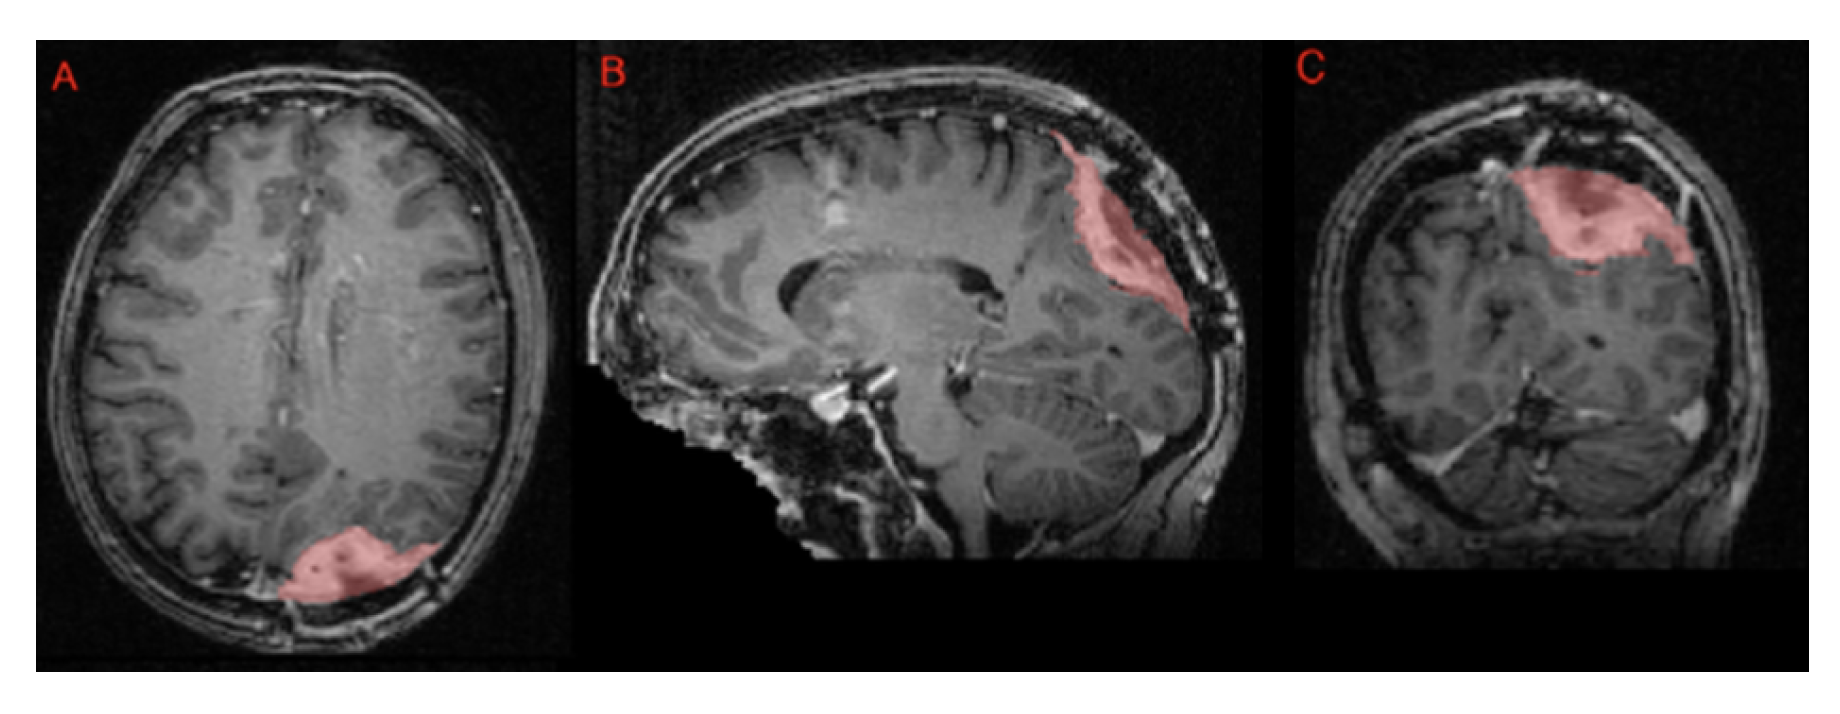

Segmentation - BraTS-Africa Dataset: All imaging data were reviewed and manually annotated by board-certified radiologists specializing in neuro-oncology, following the BraTS pre-processing and annotation protocols [10]. The new BraTS segmentation labeling introduced in 2023, and also used for the BraTS-Africa 2023 challenge, considers the following tumor sub-regions and can be visualised in Figure ii:

- Enhancing tumor (ET): Represents all tumor portions with a noticeable increase in T1 signal on post-contrast images compared to pre-contrast images, excluding adjacent blood vessels, intrinsic T1 hyperintensity, or abnormal signal in non-tumor tissues;

- Non-enhancing tumor core (NETC): Includes all non-enhancing tumor core areas, such as necrosis, cystic changes, calcification, and other non-enhancing components. Intrinsic T1 hyperintensity (e.g., intratumoral hemorrhage or fat) is also included;

- Surrounding non-enhancing FLAIR hyperintensity (SNFH): Covers the full extent of FLAIR signal abnormalities surrounding the tumor that are unrelated to the tumor core. For meningiomas, this corresponds to "vasogenic edema," excluding non-tumor-related FLAIR abnormalities like prior infarcts or microvascular ischemic changes.